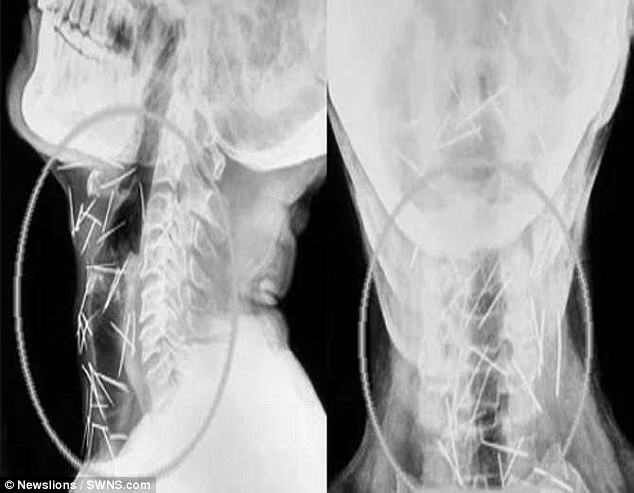

Những bức ảnh chụp x-quang về số lượng đinh khắp người ông. (Ảnh: dailymail)

Ông đã mất hơn 30kg trong quá trình tìm kiếm bệnh viện chịu tiến hành cuộc phẫu thuật lấy đinh ra khỏi cơ thể ông. Sau nỗ lực tìm kiếm, ông Badrilal đã tìm thấy các bác sĩ ở Viện Khoa học Y tế châu Á (AIMS) tại Faridabad đồng ý sẽ giúp đỡ mình lấy những cây đinh đó ra. Và đội ngũ các bác sĩ này đã tìm thấy thêm 75 cây đinh nữa. Tổng cộng, trên cơ thể người đàn ông này đã được tìm thấy 150 cây đinh - một con số gây sốc với các bác sĩ.

Người đàn ông 56 tuổi này đến từ miền Bắc Ấn Độ kiên quyết khẳng định ông không hề nhét 75 cây đinh đó vào cơ thể và không hề biết vì sao mình nó lại tồn tại trong cơ thể mình. “Khi ông ấy đến đây, tình trạng ông rất nghiêm trọng. Không thể nói chuyện, ăn uống, cơ hội sống sót rất thấp nhưng chúng tôi vẫn quyết định nhận ca bệnh đặc biệt và đầy thách thức này”, bác sĩ Parashar - Giám đốc AIMS cho biết.

Cho đến nay, sau 3 cuộc phẫu thuật, đã có 91 cây đinh được lấy ra, một số cây đã bị gỉ sét và theo các bác sĩ dự đoán, có thể nó đã tồn tại trong cơ thể ông hơn 6 tháng. Bác sĩ Lalit Mohan Parashar - người đã điều trị cho ông Badrilal - cho biết: “Để lấy những cây đinh đó ra an toàn là một thách thức lớn. Một vài cái cắm sâu vào khí quản, thực quản và cả động mạch cung cấp máu nuôi não”.